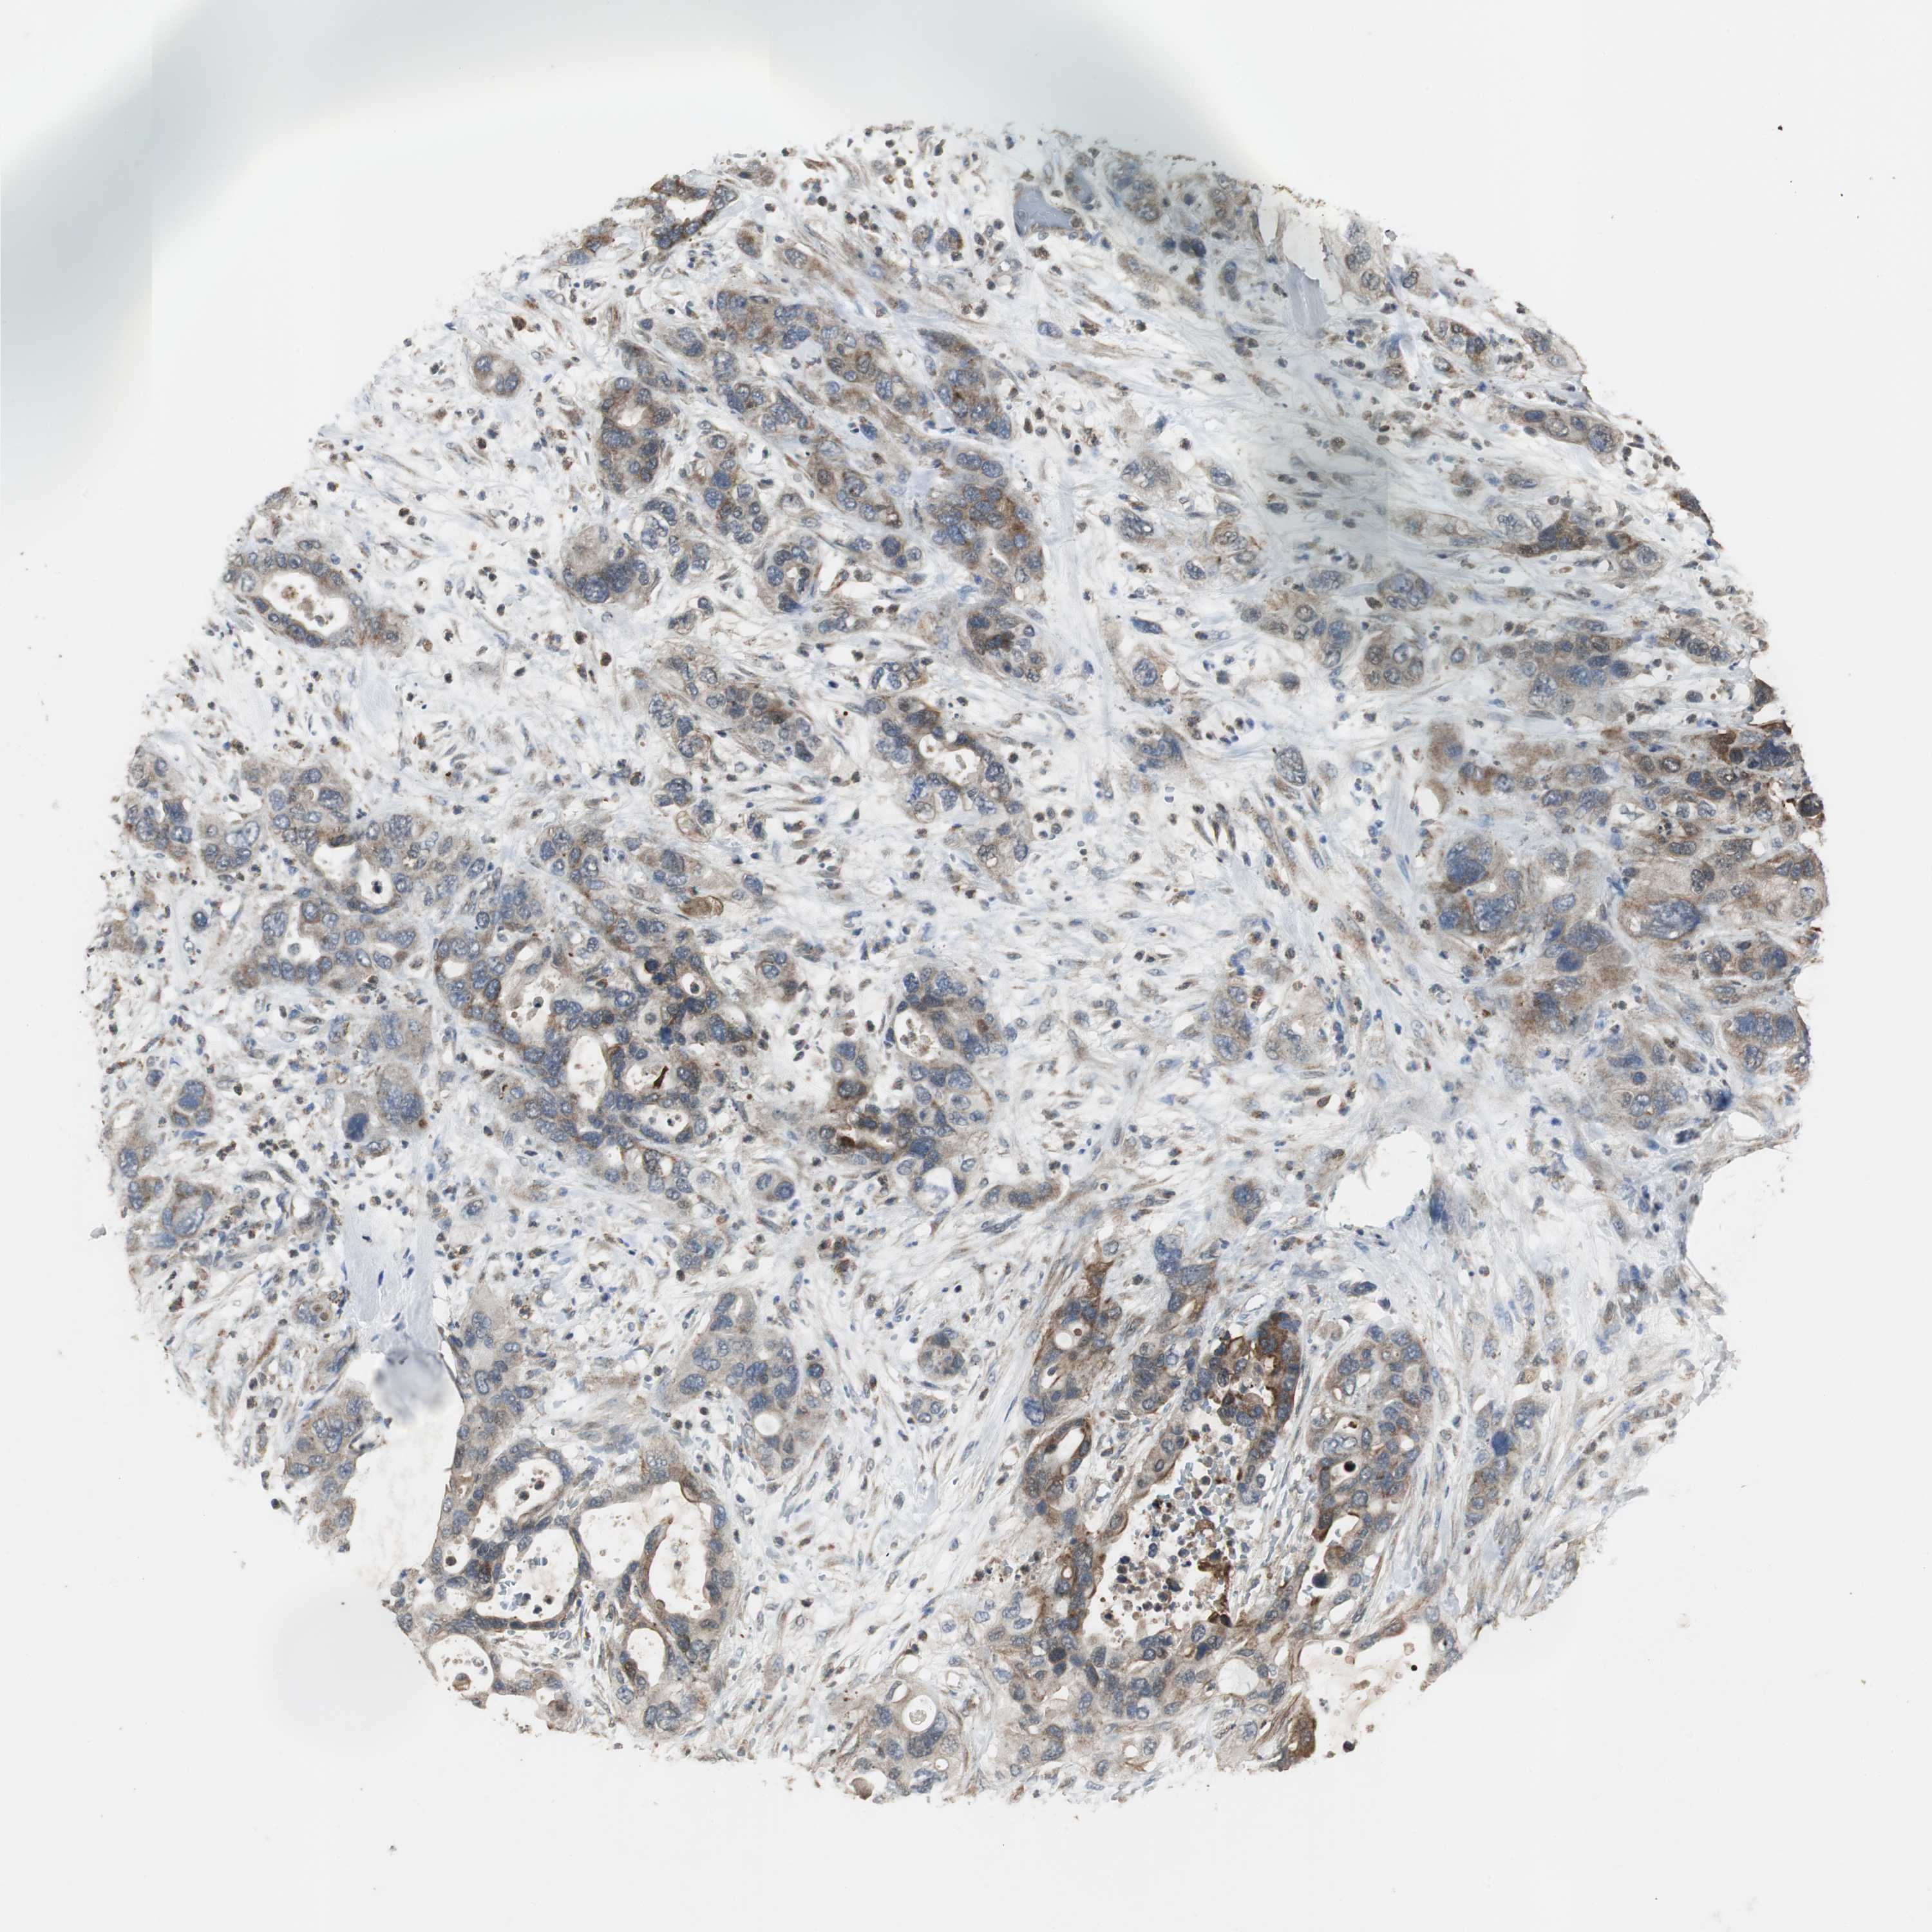

PANCREATIC CANCER - Protein expressioni

A mouse-over function shows sample information and annotation data. Click on an image to view it in a full screen mode. Samples can be filtered based on level of antibody staining by selecting one or several of the following categories: high, medium, low and not detected. The assay and annotation is described here.

Note that samples used for immunohistochemistry by the Human Protein Atlas do not correspond to samples in the TCGA dataset.

Antibody stainingi

Antibody staining in the annotated cell types in the current human tissue is reported as not detected, low, medium, or high, based on conventional immunohistochemistry profiling in selected tissues. This score is based on the combination of the staining intensity and fraction of stained cells.

Each image is clickable and will lead to virtual microscopy that enables deeper exploration of all samples and also displays staining intensity scores, fraction scores and subcellular localization as well as patient and tissue information for each sample.

Antibody HPA006514

Staining

High

Medium

Low

Not detected

Intensity

Strong

Moderate

Weak

Negative

Quantity

>75%

75%-25%

<25%

None

Location

Nuclear

Cytoplasmic/membranous

Cytoplasmic/membranous,nuclear

Adenocarcinoma, NOS

Adenocarcinoma, metastatic, NOS